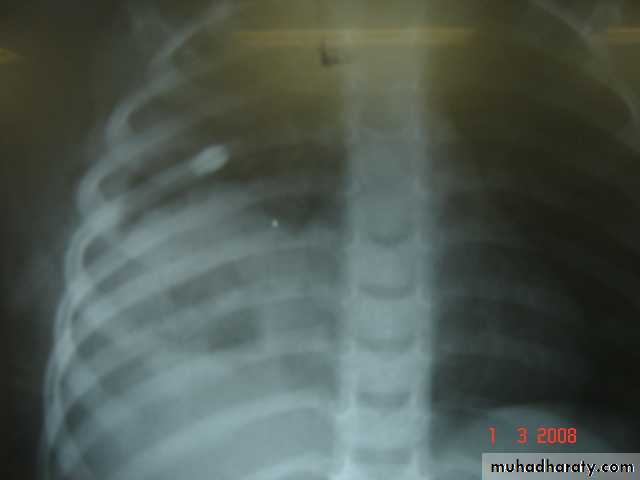

• 3-Pleurl injuries Can lead toA-Pneumothorax which can be partial or complete closed or open sucking or tension pnemothorax . B-Haemothorax may be mild or severe and may be with pneumothorax

Pneumothorax

Collapsed lungTraumatic haemothorax

Fractures